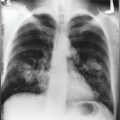

Након три године могу да кажем да рак данас није више смртоносна болест, она све више постаје хронична с којом пацијенти могу квалитетно живети, пише др Влада Комадина у рубрици „Глас пацијента“